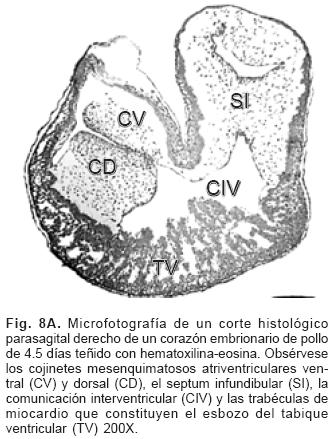

El proceso embrionario de la tabicación A–V se establece con el crecimiento y desarrollo del mesénquima cardíaco de las almohadillas endocárdicas dorsal y ventral del canal A–V que en el embrión ocurre entre los estadios (25 al 29) de Hamburguer y Hamilton17,18 (Fig. 8A), dichas almohadillas completamente desarrolladas se fusionan y conforman el tabique A–V que divide al canal A–V común en dos: derecho e izquierdo (Fig. 8B) en cuyas paredes se diferencian dos anillos fibrosos situados a desnivel, uno para la válvula tricúspide y otro para la válvula mitral (Fig. 9A). El extremo craneal de este tabique se dobla hacia la izquierda, crece dentro del canal A–V izquierdo y se transforma en el esbozo de la porción central de la valva medial (aórtica) de la válvula mitral21 (Fig. 9B), proceso que ocurre en los embriones humanos en los horizontes de Streeter del XIII al XVI.19,20 El espacio comprendido entre el tabique ventricular y la valva medial de la válvula mitral constituye el tracto de salida del ventrículo izquierdo. La valva lateral de la válvula mitral se separa como un faldón de la pared del canal A–V y del ventrículo izquierdo del que se diferencian también sus cuerdas tendinosas y músculos papilares (Fig. 9B). La válvula tricúspide se desarrolla por el mismo proceso de delaminación para conformar tres láminas de miocardio que corresponden a las valvas septal, anterior y posterior con sus respectivas cuerdas tendinosas y músculos papilares.1